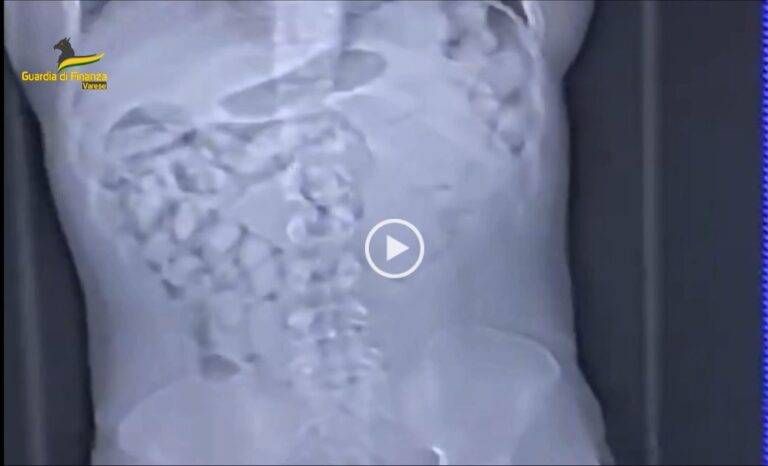

La Guardia di Finanza di Malpensa ha avviato l’operazione denominata “Ritual” con l’arresto di un passeggero di nazionalità nigeriana proveniente da Addis Abeba (Etiopia), reo di aver introdotto nel territorio nazionale oltre 1.500 grammi di cocaina, confezionata in 92 ovuli occultati nelle cavità addominali.

Il dispositivo di contrasto attuato dai finanzieri in servizio presso l’aeroporto di Malpensa ha permesso di arrestare un ulteriore corriere, una donna nigeriana residente a Torino, trovata in possesso di oltre 530 grammi di cocaina e di ricostruire altre due importazioni illecite di droga effettuate dalla stessa, poche settimane prima del suo arresto.